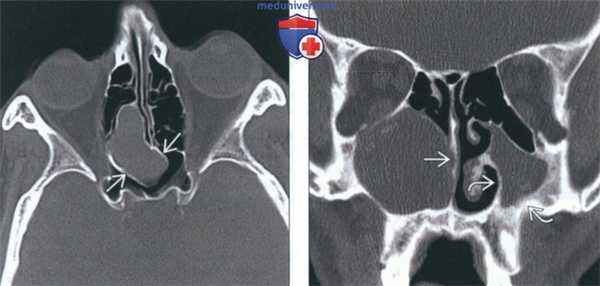

(Слева) На аксиальной КТ в костном окне определяется мукоцеле задних ячеек решетчатой пазухи, распространяющееся в сфеноидальные пазухи, но не в глазницу. Костная пластинка на периферии мукоцеле истончена и видоизменена.

(Справа) На корональной КТ в костном окне в правой верхнечелюстной пазухе (нетипичная локализация) определяется мукоцеле большого размера, приводящее к обструкции полоаи носа. Обратите внимание на признаки хронического левоаороннего гайморита: уменьшение объема пазухи и утолщение ее стенок.